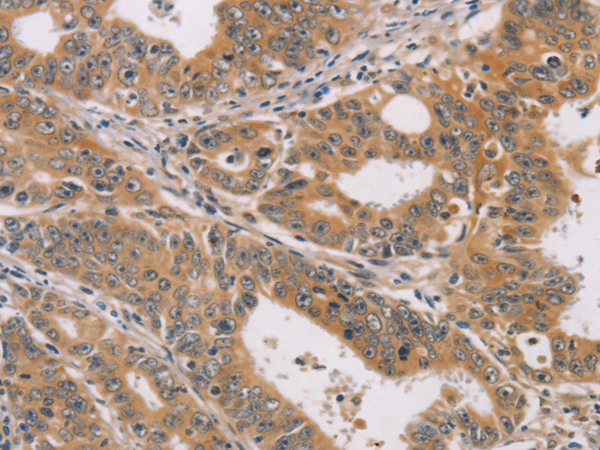

分类: 科研抗体货号: P04769别名: CD318; TRASK; SIMA135应用: WB,IHC反应种属: Human